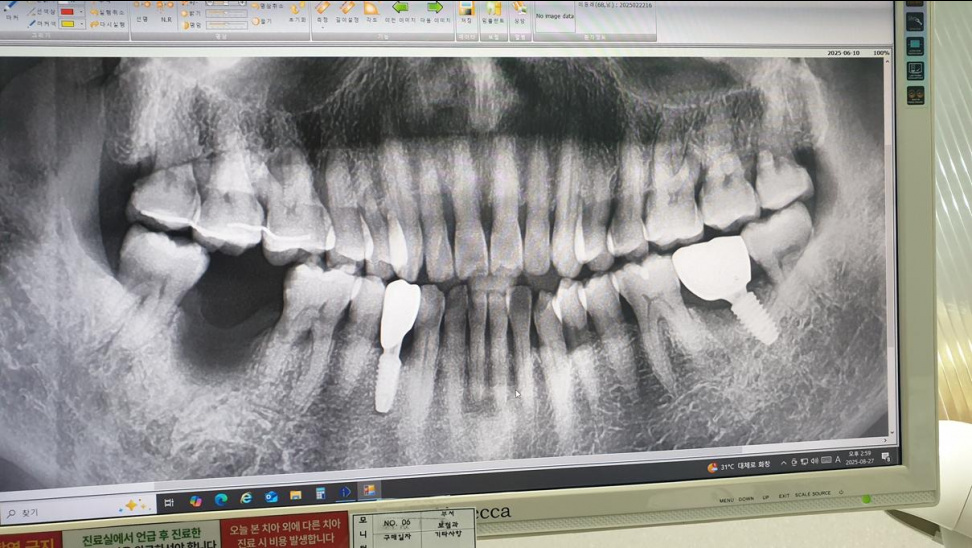

• 2026-02-20 46

• 두번째 임플란트